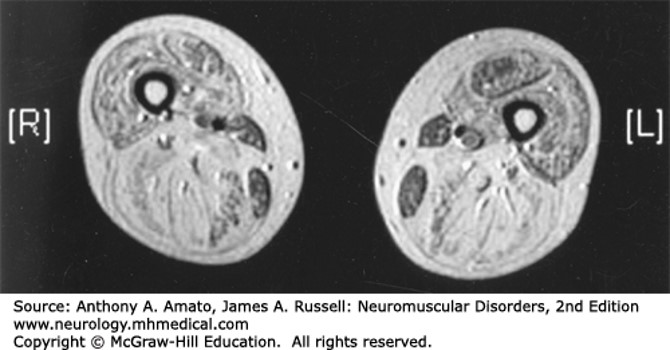

Becker muscular dystrophy. Skeletal muscle MRI (T1 weighted) of the thigh in a patient with BMD demonstrates the bright and feathery appearance of fat and connective tissue replacing muscle in the thighs.

Source: Amato AA, Russell JA. Neuromuscular Disorders, 2e; 2015.